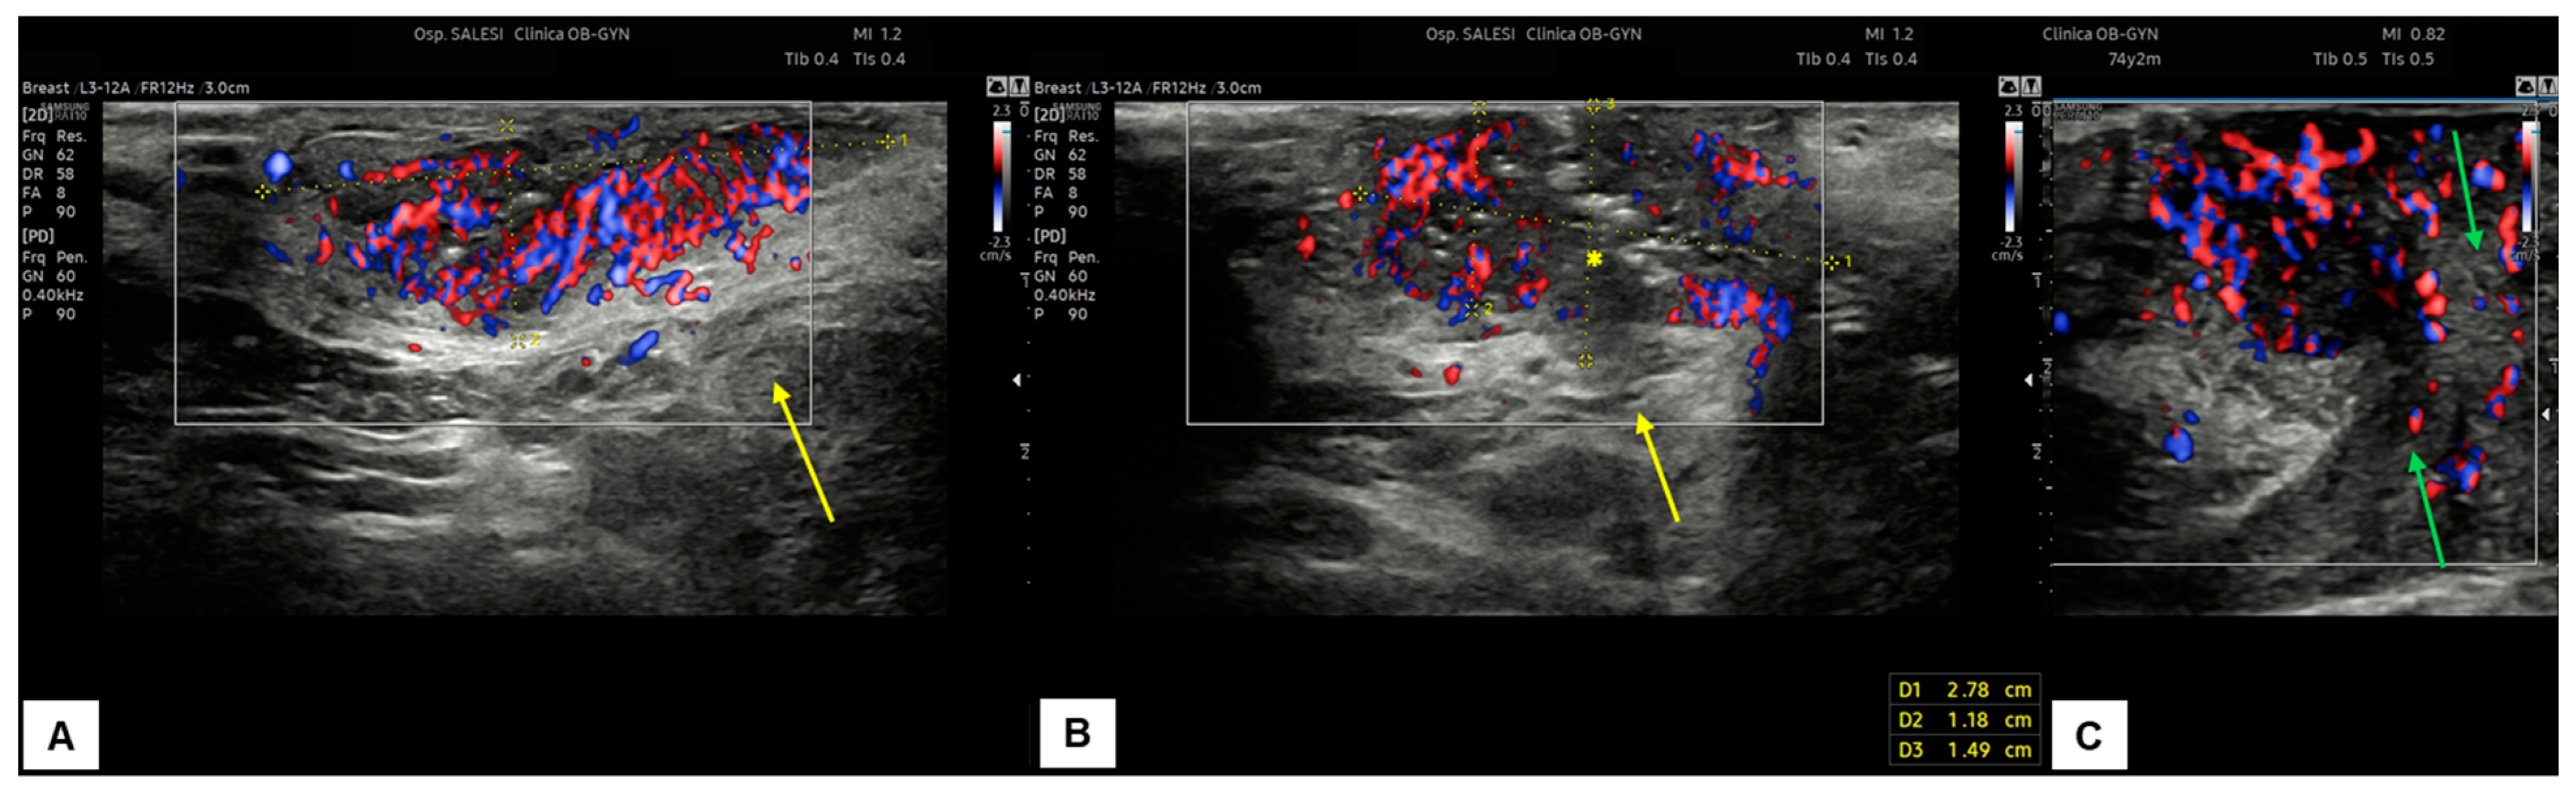

7.3. Malignant Vulvar Lesions